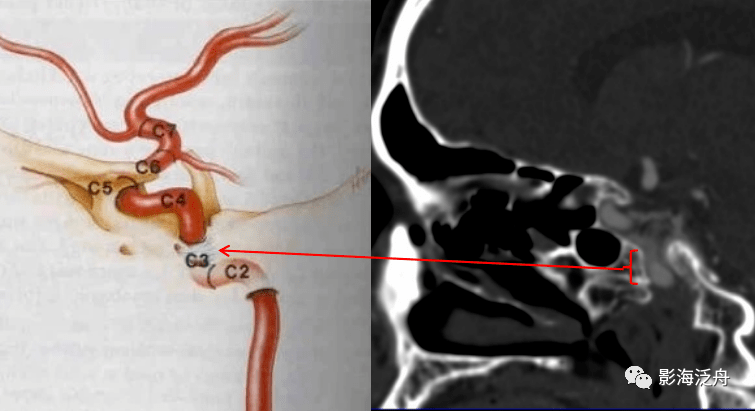

颈内动脉c6段在侧位脑血管造影显示最清楚, 在与c5段(床突段)交界处远